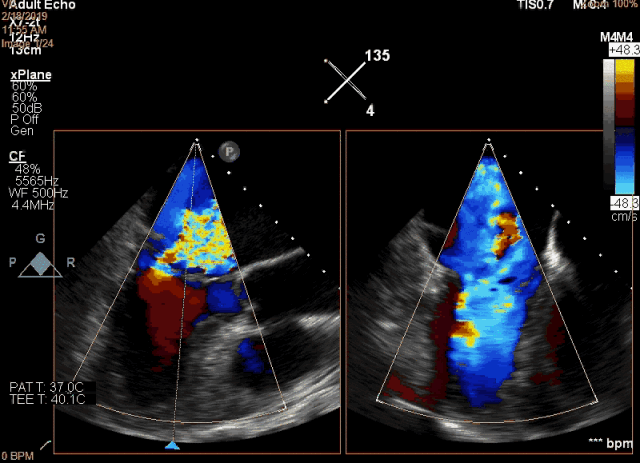

該例患者是一名78歲男性,合并癥較多,基礎(chǔ)心功能差,傳統(tǒng)外科手術(shù)風(fēng)險(xiǎn)極高,故選擇了經(jīng)心尖二尖瓣夾合術(shù)(ValveClamp)。然而,術(shù)前超聲評(píng)估顯示,患者后葉脫垂范圍極大,達(dá)23mm,P2 和P3均有脫垂,反流頸寬度達(dá)13mm。嚴(yán)重二尖瓣反流導(dǎo)致患者心功能很差,血壓較低。如此廣泛的脫垂,使用國(guó)外同類產(chǎn)品完成經(jīng)導(dǎo)管微創(chuàng)二尖瓣修復(fù)也是很有挑戰(zhàn),甚至無(wú)法完成的。葛均波院士團(tuán)隊(duì)分析患者病情后,選擇了使用我國(guó)自主研發(fā)的二尖瓣器械ValveClamp為患者實(shí)施經(jīng)心尖二尖瓣夾合術(shù)。反復(fù)嘗試數(shù)次單個(gè)夾合器夾合后,患者仍有中重度二尖瓣反流。遂采取雙夾合器技術(shù),為患者植入兩個(gè)夾合器,術(shù)后即刻患者反流減少至輕度,二尖瓣跨瓣壓差僅為3mmHg。該例手術(shù)是ValveClamp首例采取雙夾子技術(shù),證明了該器械行雙夾子技術(shù)是安全、可行的。手術(shù)由中山醫(yī)院心內(nèi)科葛均波院士、周達(dá)新教授、潘文志副主任醫(yī)師,心外科魏來教授,心超室的潘翠珍教授、李偉主治醫(yī)師,心外麻的郭克芳教授共同完成。

圖2 術(shù)前食道超聲顯示二尖瓣大范圍脫垂及極重度反流